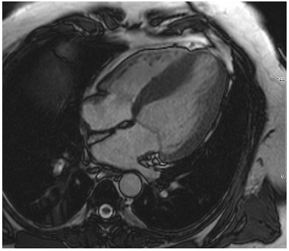

Table 3 summarises a suggested CMR scan protocol for the diagnosis of presumed HHD and differential diagnosis of patients with a “thickened left ventricle”.

Table 3.

The cardiovascular magnetic resonance protocol used for assessment of hypertensive patients. The described protocol can be acquired within 45–50 min. Images are examples from patients with hypertensive heart disease.

Similar to echocardiography, LV geometry can be assessed using relative wall thickness (RWT) and CMR-specific normal values for LV myocardial mass (Figure 2). LA dimensions can be assessed with Simpson’s biplane or area-length methods from the standard views, or more precisely with a volumetric assessment using an atrial short-axis stack. LA enlargement is a reliable marker of diastolic dysfunction (chronically elevated LV filling pressures) in the absence of mitral valve disease [31]. The recently introduced left atrial coupling index (LACI) is a ratio of the indexed left atrial end-diastolic volume (LAVI) in relation to the left ventricular end-diastolic volume (LVEDVI) [32]. This ratio may offer prognostic information regarding cardiovascular events such as atrial fibrillation, heart failure, and coronary artery disease-related death.